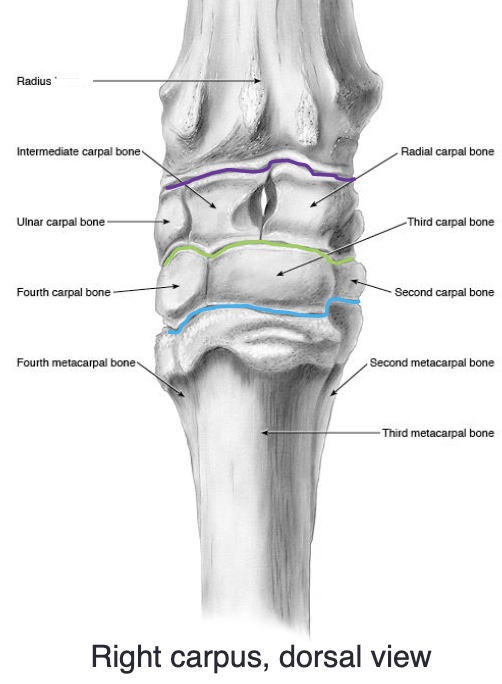

what are the names of the proximal row of carpal bones (medial to lateral)

radial, intermediate, ulnar

what are the names of the distal row of carpal bones (medial to lateral)

2nd, 3rd, 4th

what are the 3 joints of the carpus

radiocarpal (antebrachial) joint

middle/intercarpal joint

carpometacarpal joint

what two joints are the carpus are in communication with e/o

middle/intercarpal joint & carpometacarpal joint

“down in front”

identify the image

purple- radiocarpal joint

green- middle/intercarpal joint

blue- carpometacarpal joint

proximal row of carpal bones: radial, intermediate, ulnar

distal row of carpal bones: 2, 3, 4

(medial to lateral)

the accessory carpal bone is medial or lateral

lateral

what is desensitized in radiocarpal joint

joint

what is desensitized in middle/intercarpal joint

middle/intercarpal joint + carpometacarpal joint